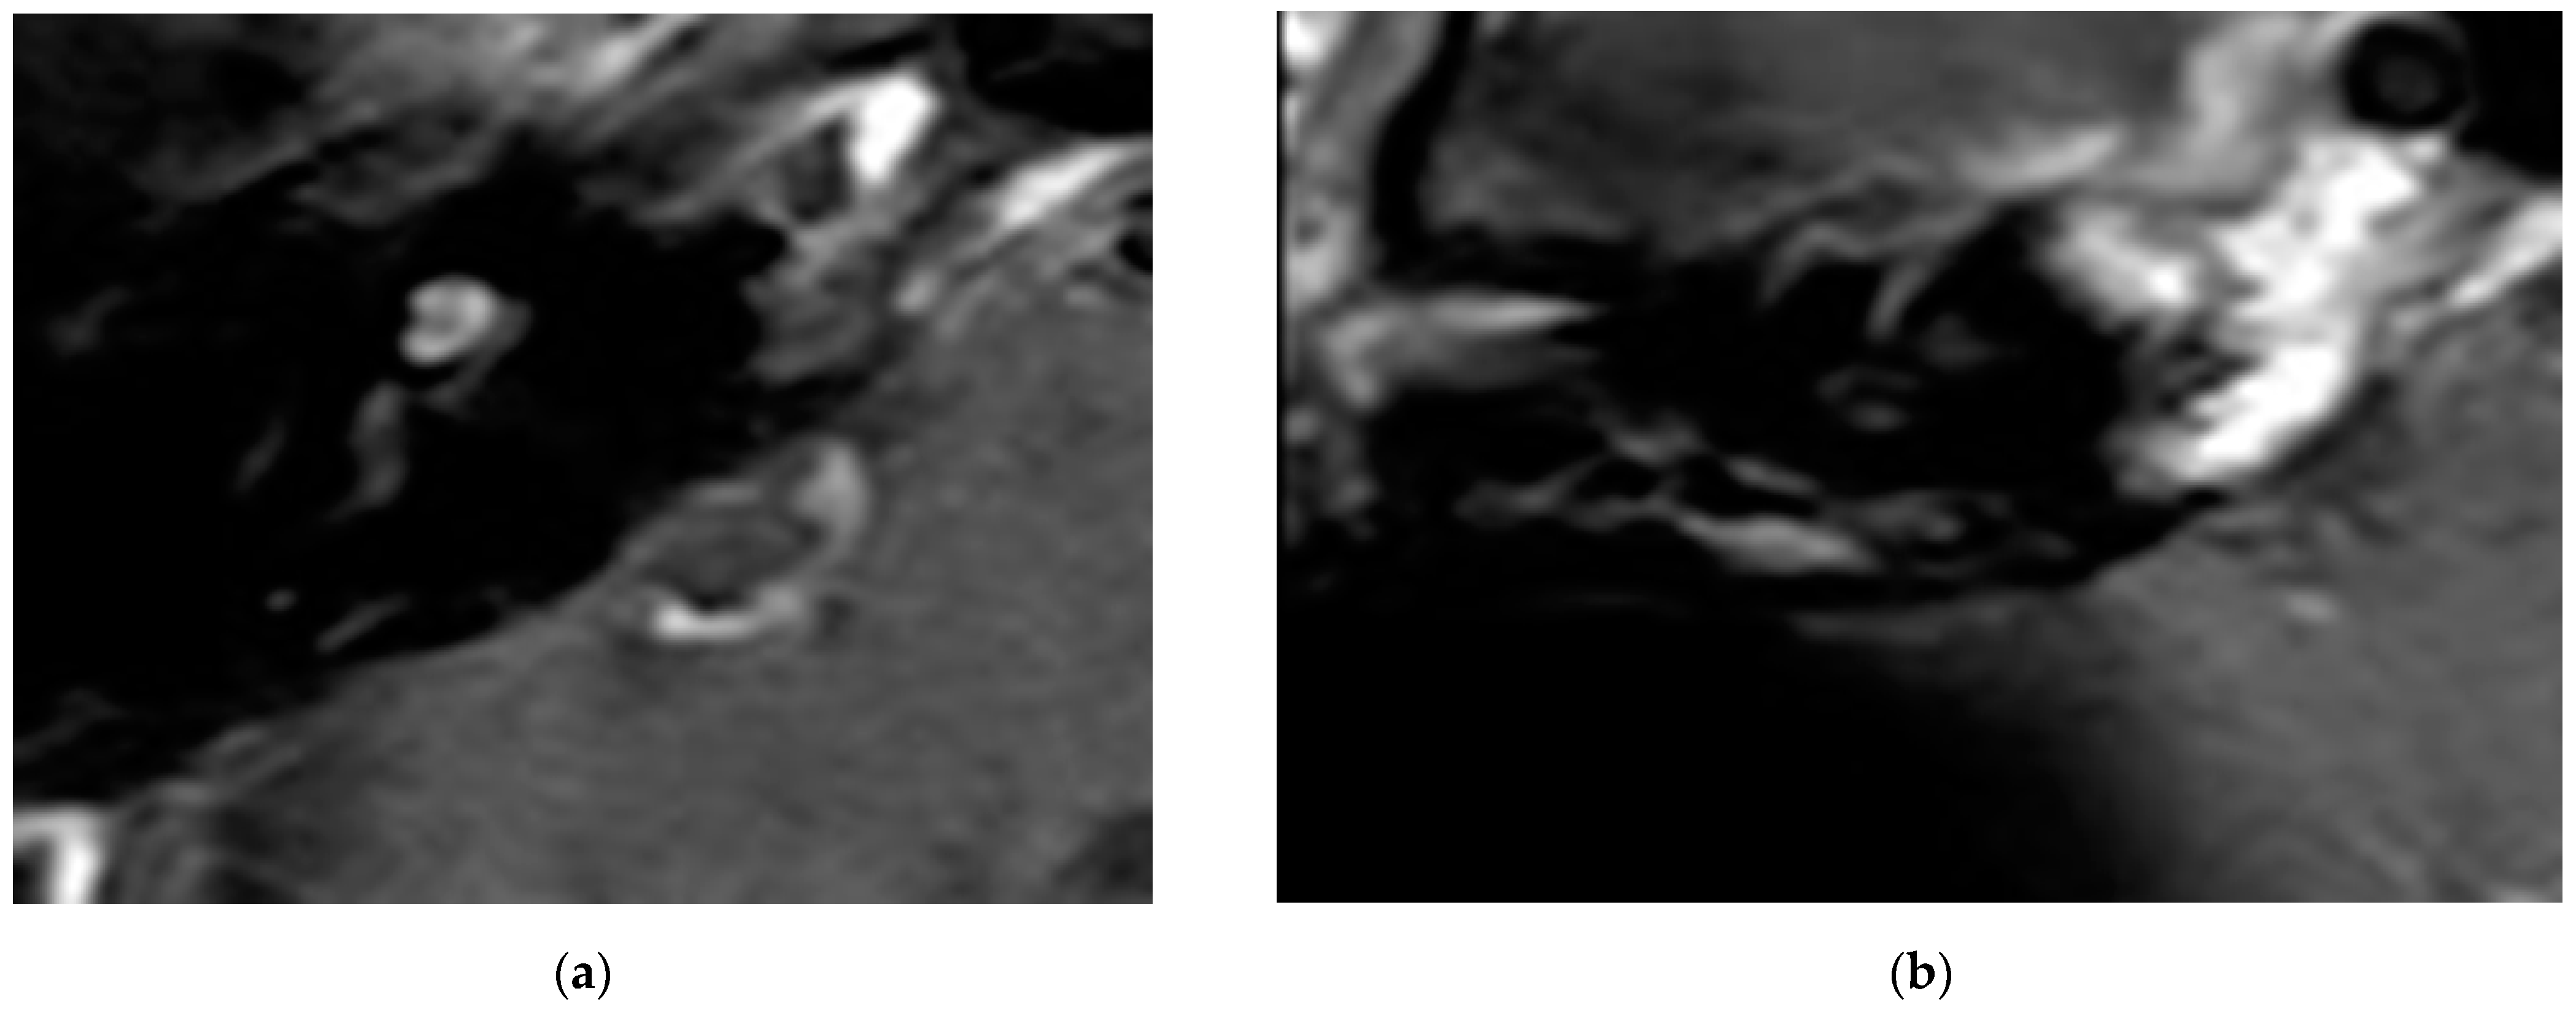

In all cases, the cochlea and the IAC were visually accessible. In all cases, complete removal of the intracochlear ILS vestibular parts was confirmed by the MRI. The individual pre- and postoperative MRI T1 Gad figures are exemplary for case 4 and 6 (Figure 2 and Figure 3). In Figure 4b, an initially radiologically missed or residual tumor at the IAC fundus from the vestibulum (transmacular) is shown (case 5), as well as an additional signal in the basal turn.

Figure 2.

(a). An exemplary ILS tumor pre-op (T1, Gad). (b). The ILS region with a T1 Gad sequence after removal and CI.

Figure 3.

(a). The exemplary ILS pre-op (T1, Gad); (b). The ILS region with a T1 Gad sequence after removal and CI.